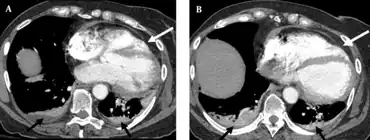

Contrast enhanced chest CT in individual with blunt cardiac injury in axial plane at the level of descending thoracic aorta- a,b) demonstrate rupture of left lateral pericardium with altered axis of heart.